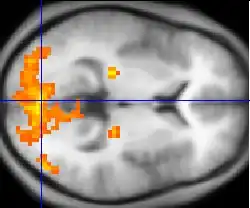

A ressonância magnética funcional (FMRI) e a rotulagem de rotação arterial (ASL) dependem das propriedades paramagnéticas da hemoglobina oxigenada e desoxigenada para ver imagens de alteração do fluxo sanguíneo no cérebro associado à atividade neural. Isso permite a geração de imagens que refletem quais estruturas cerebrais são ativadas (e como) durante o desempenho de diferentes tarefas ou em estado de repouso. De acordo com a hipótese de oxigenação, as mudanças no uso de oxigênio no fluxo sanguíneo cerebral regional durante a atividade cognitiva ou comportamental podem ser associadas aos neurônios regionais como diretamente relacionados às tarefas cognitivas ou comportamentais atendidas.

A maioria dos scanners de FMRI permite que os indivíduos sejam apresentados com diferentes imagens visuais, sons e estímulos de toque, e para fazer diferentes ações, como pressionar um botão ou mover um joystick. Consequentemente, o FMRI pode ser usado para revelar estruturas cerebrais e processos associados à percepção, pensamento e ação. A resolução do FMRI é de aproximadamente 2-3 milímetros no presente, limitada pela disseminação espacial da resposta hemodinâmica à atividade neural. Ele substituiu em grande parte o PET para o estudo dos padrões de ativação cerebral. O PET, no entanto, retém a vantagem significativa de ser capaz de identificar receptores específicos do cérebro (ou transportadores) associados a neurotransmissores específicos através da sua capacidade de imagem de "ligandos" de receptores radiomarcados (os ligandos do receptor são quaisquer produtos químicos que se encaixam nos receptores).

Além da pesquisa em assuntos saudáveis, o FMRI é cada vez mais utilizado para o diagnóstico médico da doença. Como o FMRI é esquisitamente sensível ao uso de oxigênio no fluxo sanguíneo, é extremamente sensível às mudanças iniciais no cérebro resultantes da isquemia (fluxo sanguíneo anormalmente baixo), como as mudanças que se seguem ao AVC. O diagnóstico precoce de certos tipos de acidente vascular cerebral é cada vez mais importante na neurologia, uma vez que as substâncias que dissolvem coágulos sanguíneos podem ser usadas nas primeiras horas após a ocorrência de certos tipos de acidente vascular cerebral, mas são perigosas para uso posterior. As alterações cerebrais observadas no FMRI podem ajudar a tomar a decisão de tratar com esses agentes. Com uma precisão de 72% a 90%, onde a chance alcançaria 0,8%,[15] as técnicas de FMRI podem decidir qual de um conjunto de imagens conhecidas que o sujeito está visualizando.[16]